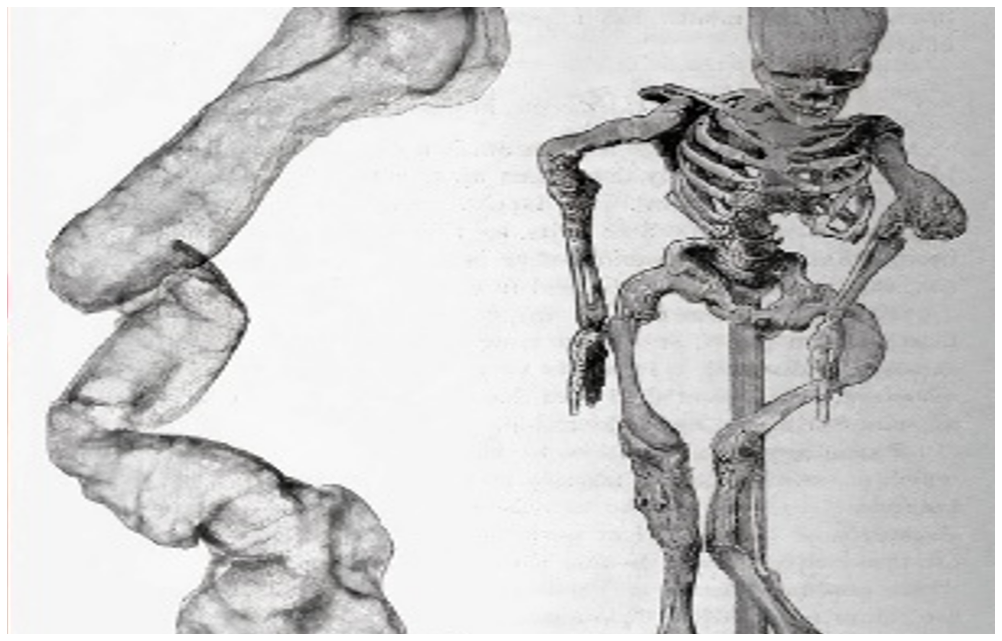

Қазіргі уақытта әртүрлі этиологиялы сүйек тінінің ақауларының стандартты емі оны ауто- немесе аллотрансплантатпен толтыру болып табылады. Алайда, пайдаланылатын аллотрансплантаттардың басым бөлігі сырттан әкелінетін болған соң көп жағдайда Қазақстан Республикасының дәрілік заттардың, медициналық мақсаттағы бұйымдар мен медициналық техниканың мемлекеттік тізілімінде тіркелмеген болып келеді. Бұл жағдай осы препараттарды Қазастанда қолдануды қиындатады. Ортопедиялық оталарға арналған шетелдік сүйек-пластикалық материалдардың жоғары құнын атап өткен тағы жөн, сонымен қатар ақауларды ауыстыру кезінде бұл препараттардың үлкен көлемі қажет болады. Остеоиндукторлық заттармен байытылған дуплексті отандық остеопластикалық материалды жасау сүйек ақаулары мен жалған буындары бар науқастарды емдеуге, мүгедектікті азайтуға, бір науқасты емдеу құнын төмендетуден экономикалық тиімділік алуға және препаратты жақын және алыс шетелдерге экспорттау мүмкіндігін береді.

Жүргізілген салыстырмалы зерттеу негізінде сүйек ақауларын толтыратын және жергілікті сүйек регенерациясын күшейтетін сүйек тінінің ақауларын емдеу әдісі әзірленеді. Бұл әдіс сүйектерді қалпына келтіру оталарының сапасын жақсартады. Бұл зерттеудің экономикалық тиімділігі - жамбас буынының эндопротездеуден кейін науқастардан алынған ортан жілік басынан аллографттарды өзіміз өндіру арқылы, аллографтты сатып алу құнын төмендету. Жоғарыда аталғандар шетелдік өндірушілерден сүйек тінін сатып алу құнын төмендетеді, Қазақстан Республикасында отандық сүйек аллографттарын өндіруге жағдай жасайды, жарақат және ортопедиялық бөлімшелерде қауіпсіз донорлық сүйекке деген қажеттілікті өтейді. Остеогенезді ынталандыру травматология мен ортопедияда емдеудің жаңа технологиясын алуға, ауруханаға жатқызу ұзақтығын қысқартуға, мүгедектікті азайтуға мүмкіндік береді, бұл экономикалық ғана емес, сонымен бірге әлеуметтік нәтиже береді.

2023 жылы сүйек ақауының жазылу динамикасын анықтау үшін гистологиялық зерттеу жүргізілді. Осы мақсатта 5 топ (әрқайсысы 30 қоян) құрылды: 1 топ – PRP бар аллографт; 2 топ – бисфосфанат қосылған аллографт; 3-топ – BMP-2 бар аллографт; 4 - BMP-2+ бисфосфонаты бар аллографт; 5-топ – аллографт қана. Оларға ортан жілігінің ақауының үлгісін қалыптастыру үшін ота жасалды. Топтардағы ақаулар әртүрлі биологиялық ыдырайтын материалдармен толтырылды. Бағалау 14 және 30 күндері жүргізілді. Гистологиялық талдау нәтижелері сүйек ақауы регенерациясының PRP және BMP-2 топтарында жаңадан пайда болған сүйек тінінің басым болуымен қарқынды жүретінін көрсетеді. BMP-2+бисфосфонат және тек бисфосфонат тобында сүйек ақауы негізінен фиброз тінімен жабылған.